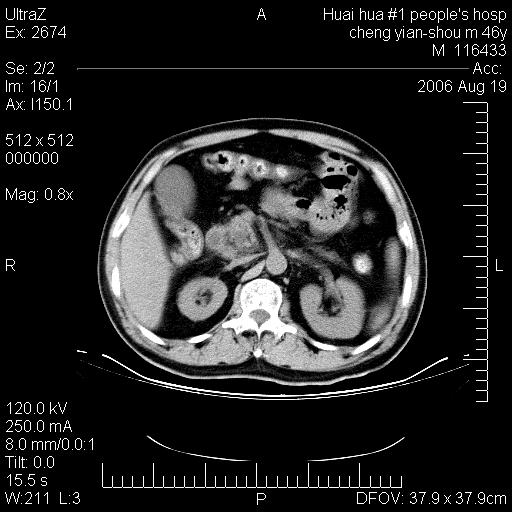

患者,男,46y。腹痛2月,消瘦。

十二指肠水平段占位,考虑间质瘤或平滑肌瘤。

肿块较大,腹膜后占位,境界欠清,周边脂肪密度较高呈条状影,有没有脂肪肉瘤可能,

缺少完整的三期图像。考虑肠系膜脂膜炎mp(肿块型)。

鉴别:间质瘤(这么大而无囊变不可思议)、平滑肌瘤/肉瘤、淋巴瘤、类癌,脂肪类肿瘤、转移瘤等。

十二指肠水平段占位,考虑间质瘤。

首先考虑小肠间质瘤。

十二指肠水平段软组织密度占位,考虑间质瘤可能性大。

腹膜后占位,境界欠清,考虑来源于十二指肠病变,间质瘤或平滑肌肉瘤可能性大。建议活检。

手术病理结果:原发性小肠恶性淋巴瘤(primary gastrointestinal lymphoma,pgil)是原发于胃肠的淋巴网织系统的恶性肿瘤,在结外淋巴瘤中居第一位,该病少见,临床无特异性,诊断困难,术前主要依靠影像学诊断。胃肠道本身具有较丰富的淋巴组织,因而胃肠原发性淋巴瘤是结外淋巴瘤最常见的部位,文献报道约占胃肠道恶性肿瘤的1%~4%,其中胃约占50%~70%,小肠约占35%~70%,结肠约占4%~6%。影像检查在pgil的诊断及分期中有重要的作用,ct是很有价值的检查方法。

胃肠淋巴瘤病理特点:胃肠道原发性淋巴瘤起源于胃肠壁固有层和黏膜下层的淋巴组织即胃肠粘膜相关淋巴组织(malt),多为粘膜相关淋巴瘤。病理上通常为非霍奇金淋巴瘤,且决大多数来源于b淋巴细胞,很少见于霍奇金淋巴瘤。胃肠原发淋巴瘤比胃肠道癌的发病率要低的多,最常见于胃,其病因可能跟幽门螺杆菌感染有关。幽门螺杆菌能引起胃粘膜损害,引起炎性及免疫反应,淋巴细胞聚集并形成滤泡,可影响胃的正常生理功能,导致胃淋巴瘤的发生。单纯性小肠淋巴瘤是常见好发于回盲末端,受累的肠段较长,可单发、多发,甚至累及整个小肠。原发性大肠淋巴瘤罕见,以直肠和盲肠最多见。病变大体观可表现为胃肠腔内外的肿块,也可表现为从黏膜下到浆膜面肠壁的纵向浸润,并且常常伴有肠系膜淋巴结肿大。任何情况下,肿瘤几乎总是导致一定程度的肠壁增厚,可对称或不对称,病变与正常组织间常无明确分界,肠腔可狭窄、正常或动脉瘤样扩张,后者主要是肿瘤在肠壁内浸润,破坏肠壁内植物神经丛所致。以上改变成为ct检测病变的病理基础。

肠道淋巴瘤的ct表现分为4类

1) 壁内浸润型, (2)多发结节型, (3)肠系膜受累伴腔外肿块型(本型就是),(4)肿块型。